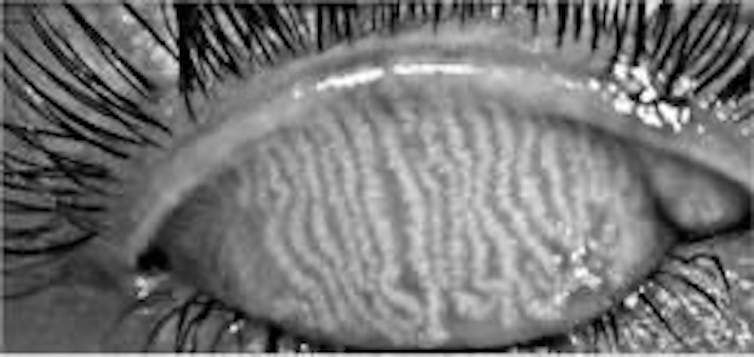

Es muy frecuente la obstrucción o la alteración en la función de las glándulas de meibomio. Esto conlleva que la lágrima carezca de ese componente graso localizado en la parte exterior de la superficie del ojo al parpadear. Como consecuencia, el ingrediente acuoso se evapora y nos produce lo que se denomina ojo seco evaporativo.

Por contraposición, una anomalía en la secreción del componente acuoso produciría el ojo seco acuodeficiente. En cualquier caso, la incomodidad estará presente en todos los ojos secos, aunque las causas sean diferentes.